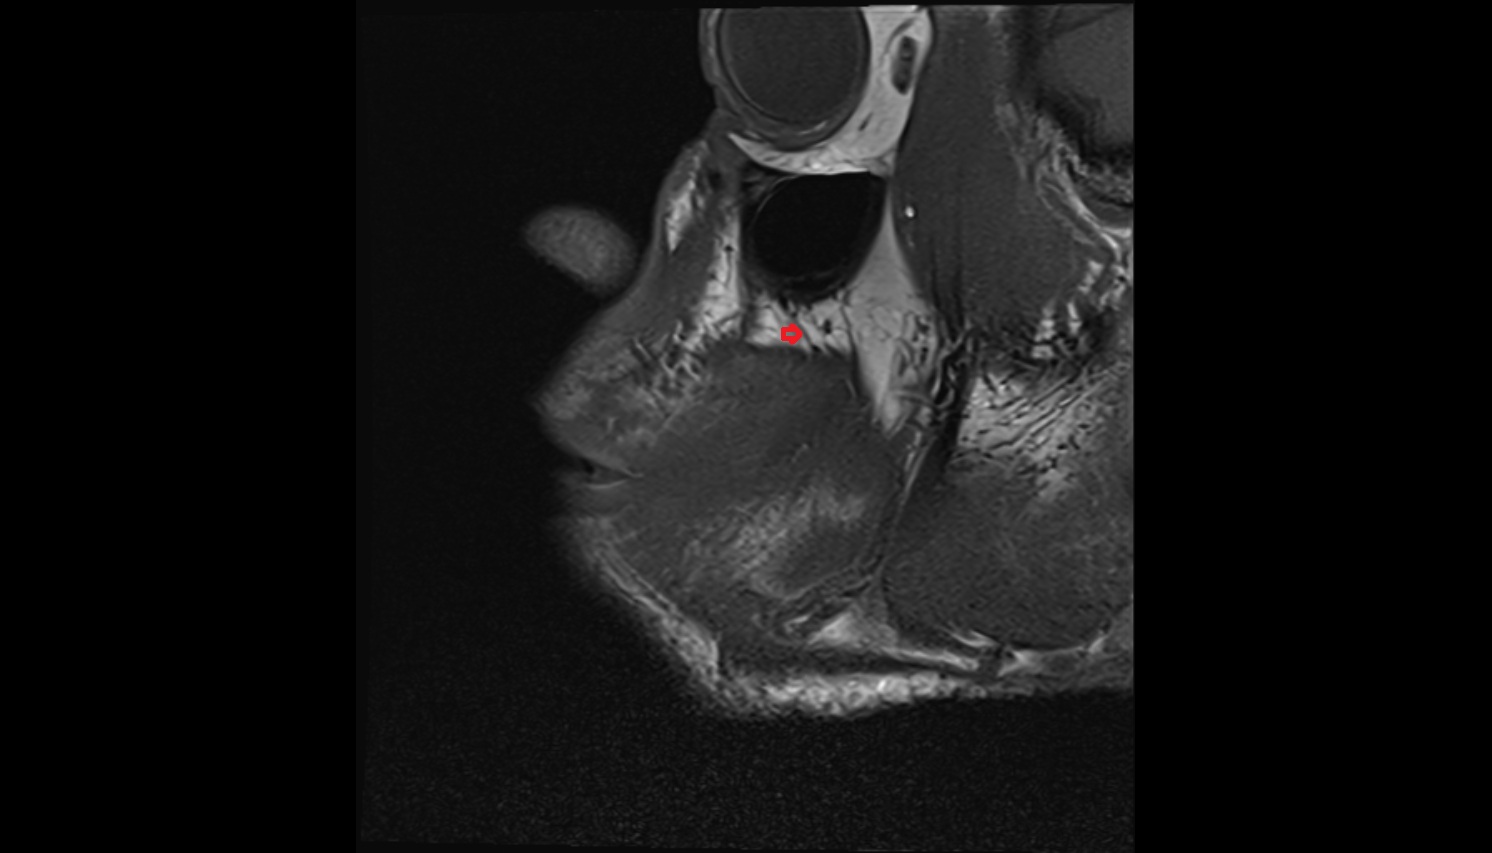

- Temporomandibular joint

- Mandibular condyle

- Mandibular fossa

- Articular disc of temporomandibular joint

- Articular eminence